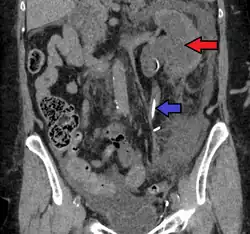

CT scan of bilateral hydronephrosis due to a bladder cancer -

Massive hydronephrosis as marked by the arrow -